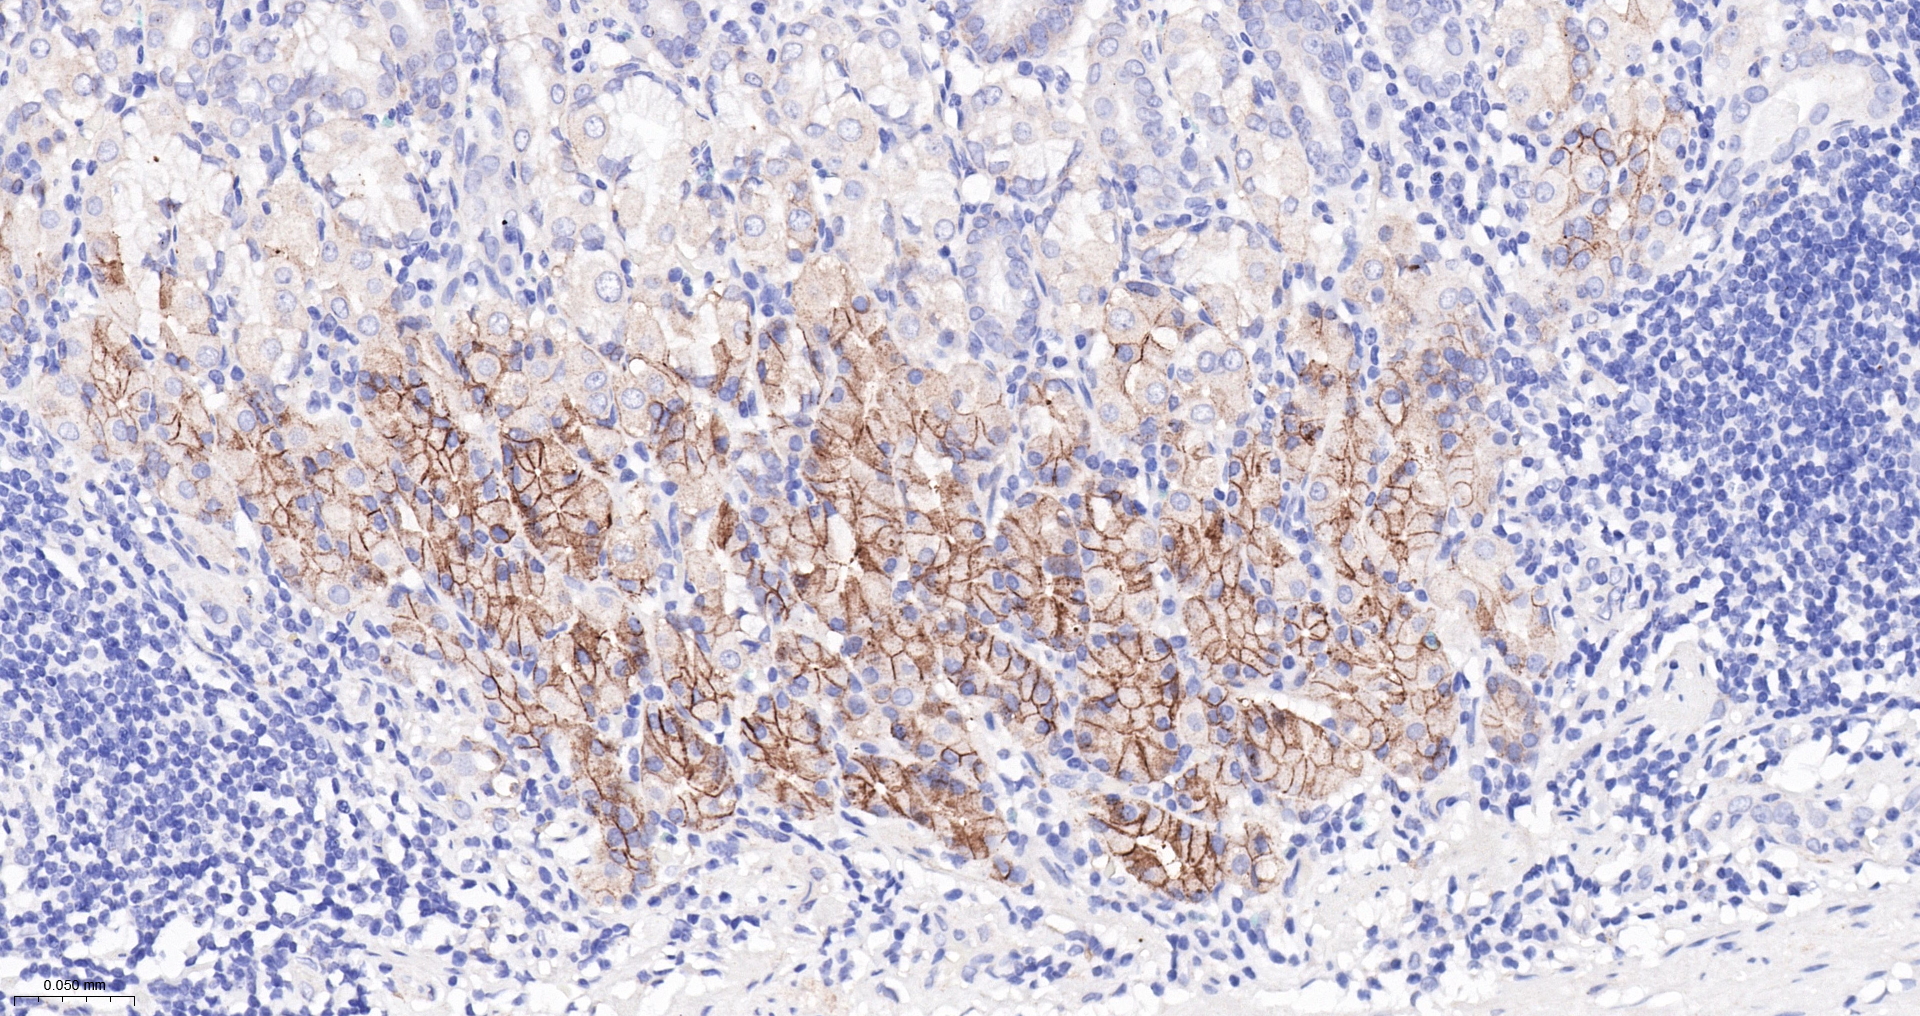

CA9 Recombinant Antibody

• IHC-P

Applications WB, IHC-P, IHC-F, IF(IHC-P)

IHC-P IHC-P1:200-800